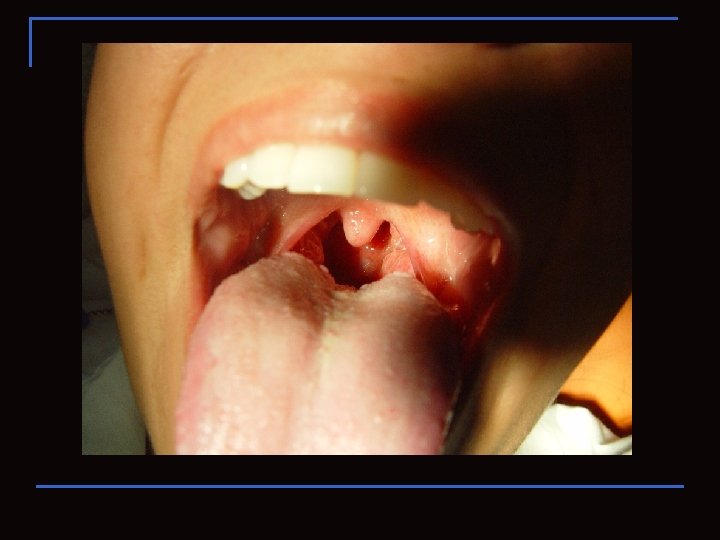

Paladares e istmo de las fauses